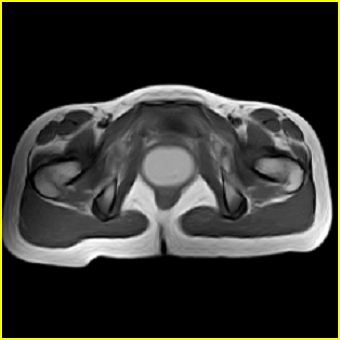

女、15岁、下腹疼痛2天,排尿困难1天。查体:处女膜闭锁,距处女膜约4至5cm处扪及一约5cm直径的圆形包块,张力较高,触痛明显、欠活动。b超提示子宫增大伴宫内增强回声团。

影像意见:子宫直肠陷凹积血。

更正影像意见:阴道积血。

处女膜闭锁,阴道积血

处女膜闭锁,阴道积血,子宫积血.

先天性处女膜闭锁,伴阴道积血,不除外先天性阴道粘液囊肿形成。

阴道积血,子宫积血.

子宫及阴道积血。

处女膜闭锁,伴子宫及阴道积血.